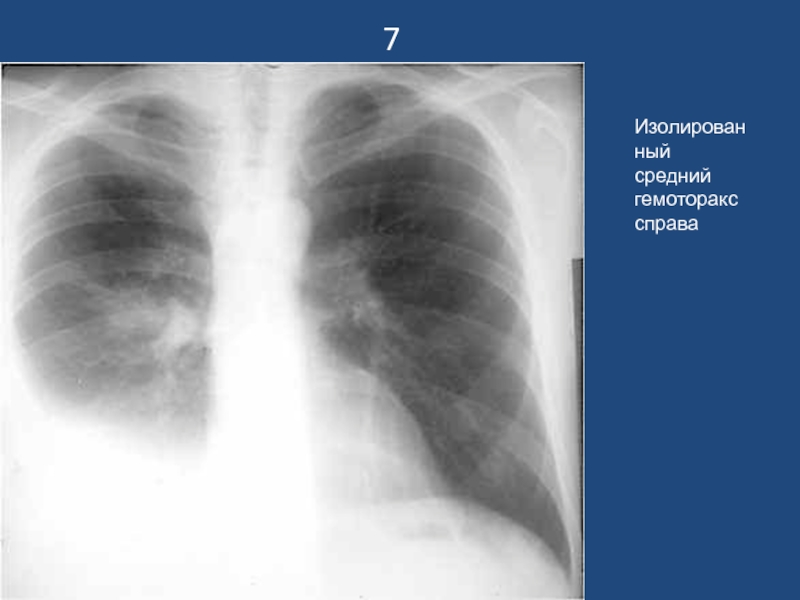

Изолированный средний гемоторакс справа

7Изолированный средний гемоторакс справа